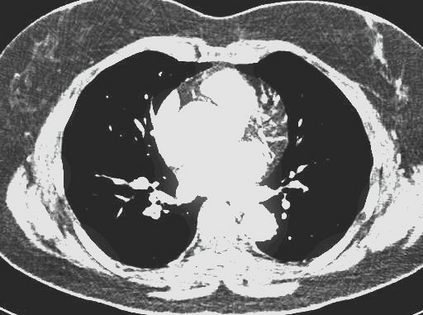

The evaluation of infectious disease processes on radiologic images is an important and challenging task in medical image analysis. Pulmonary infections can often be best imaged and evaluated through computed tomography (CT) scans, which are often not available in low-resource environments and difficult to obtain for critically ill patients. On the other hand, X-ray, a different type of imaging procedure, is inexpensive, often available at the bedside and more widely available, but offers a simpler, two dimensional image. We show that by relying on a model that learns to generate CT images from X-rays synthetically, we can improve the automatic disease classification accuracy and provide clinicians with a different look at the pulmonary disease process. Specifically, we investigate Tuberculosis (TB), a deadly bacterial infectious disease that predominantly affects the lungs, but also other organ systems. We show that relying on synthetically generated CT improves TB identification by 7.50% and distinguishes TB properties up to 12.16% better than the X-ray baseline.